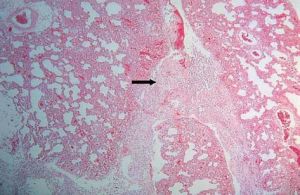

組織病理:

1.典型異物反應為巨噬細胞及異物巨細胞包圍異物,細胞質內可見有吞噬的異物,尚可見異物如縫線、液狀石蠟油、矽鹽毛髮等均可引起異物反應。

2.異物過敏反應,可出現上皮樣細胞構成的結核樣結節,具有巨細胞及乾酪樣壞死,但缺乏或少有吞噬異物現象鈷鈹或紋身顏料可引起異物過敏反應。

3.一些特異性異物肉芽腫,如紋身肉芽腫可見顏料顆粒矽肉芽腫為非結核性肉芽腫為多數巨噬細胞和多核細胞的炎症浸潤,可見折光性強的針狀矽結晶。